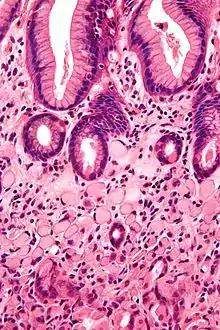

| A signet ring cell, as seen in a case of colon adenocarcinoma with mucinous features, showing a tumor cell with a vacuole of mucin. H&E stain. | |

SRCCs are named due to their resemblance to signet rings, which result from the formation of large vacuoles full of mucin that displaces the nucleus to the cell's periphery.[16]

Stomach cancers with both adenocarcinoma and some SRC (known as mixed-SRCC) exhibit more aggressive behavior than purely SRCC or non-SRCC histologies.[17]

A study of SRCC colorectal cancers compared mucin-rich SRCC tumors and mucin-poor SRCC tumors. They concluded that the latter more frequently demonstrated adverse histologic features such as lymphatic invasion, venous invasion and perineural invasion.[18]